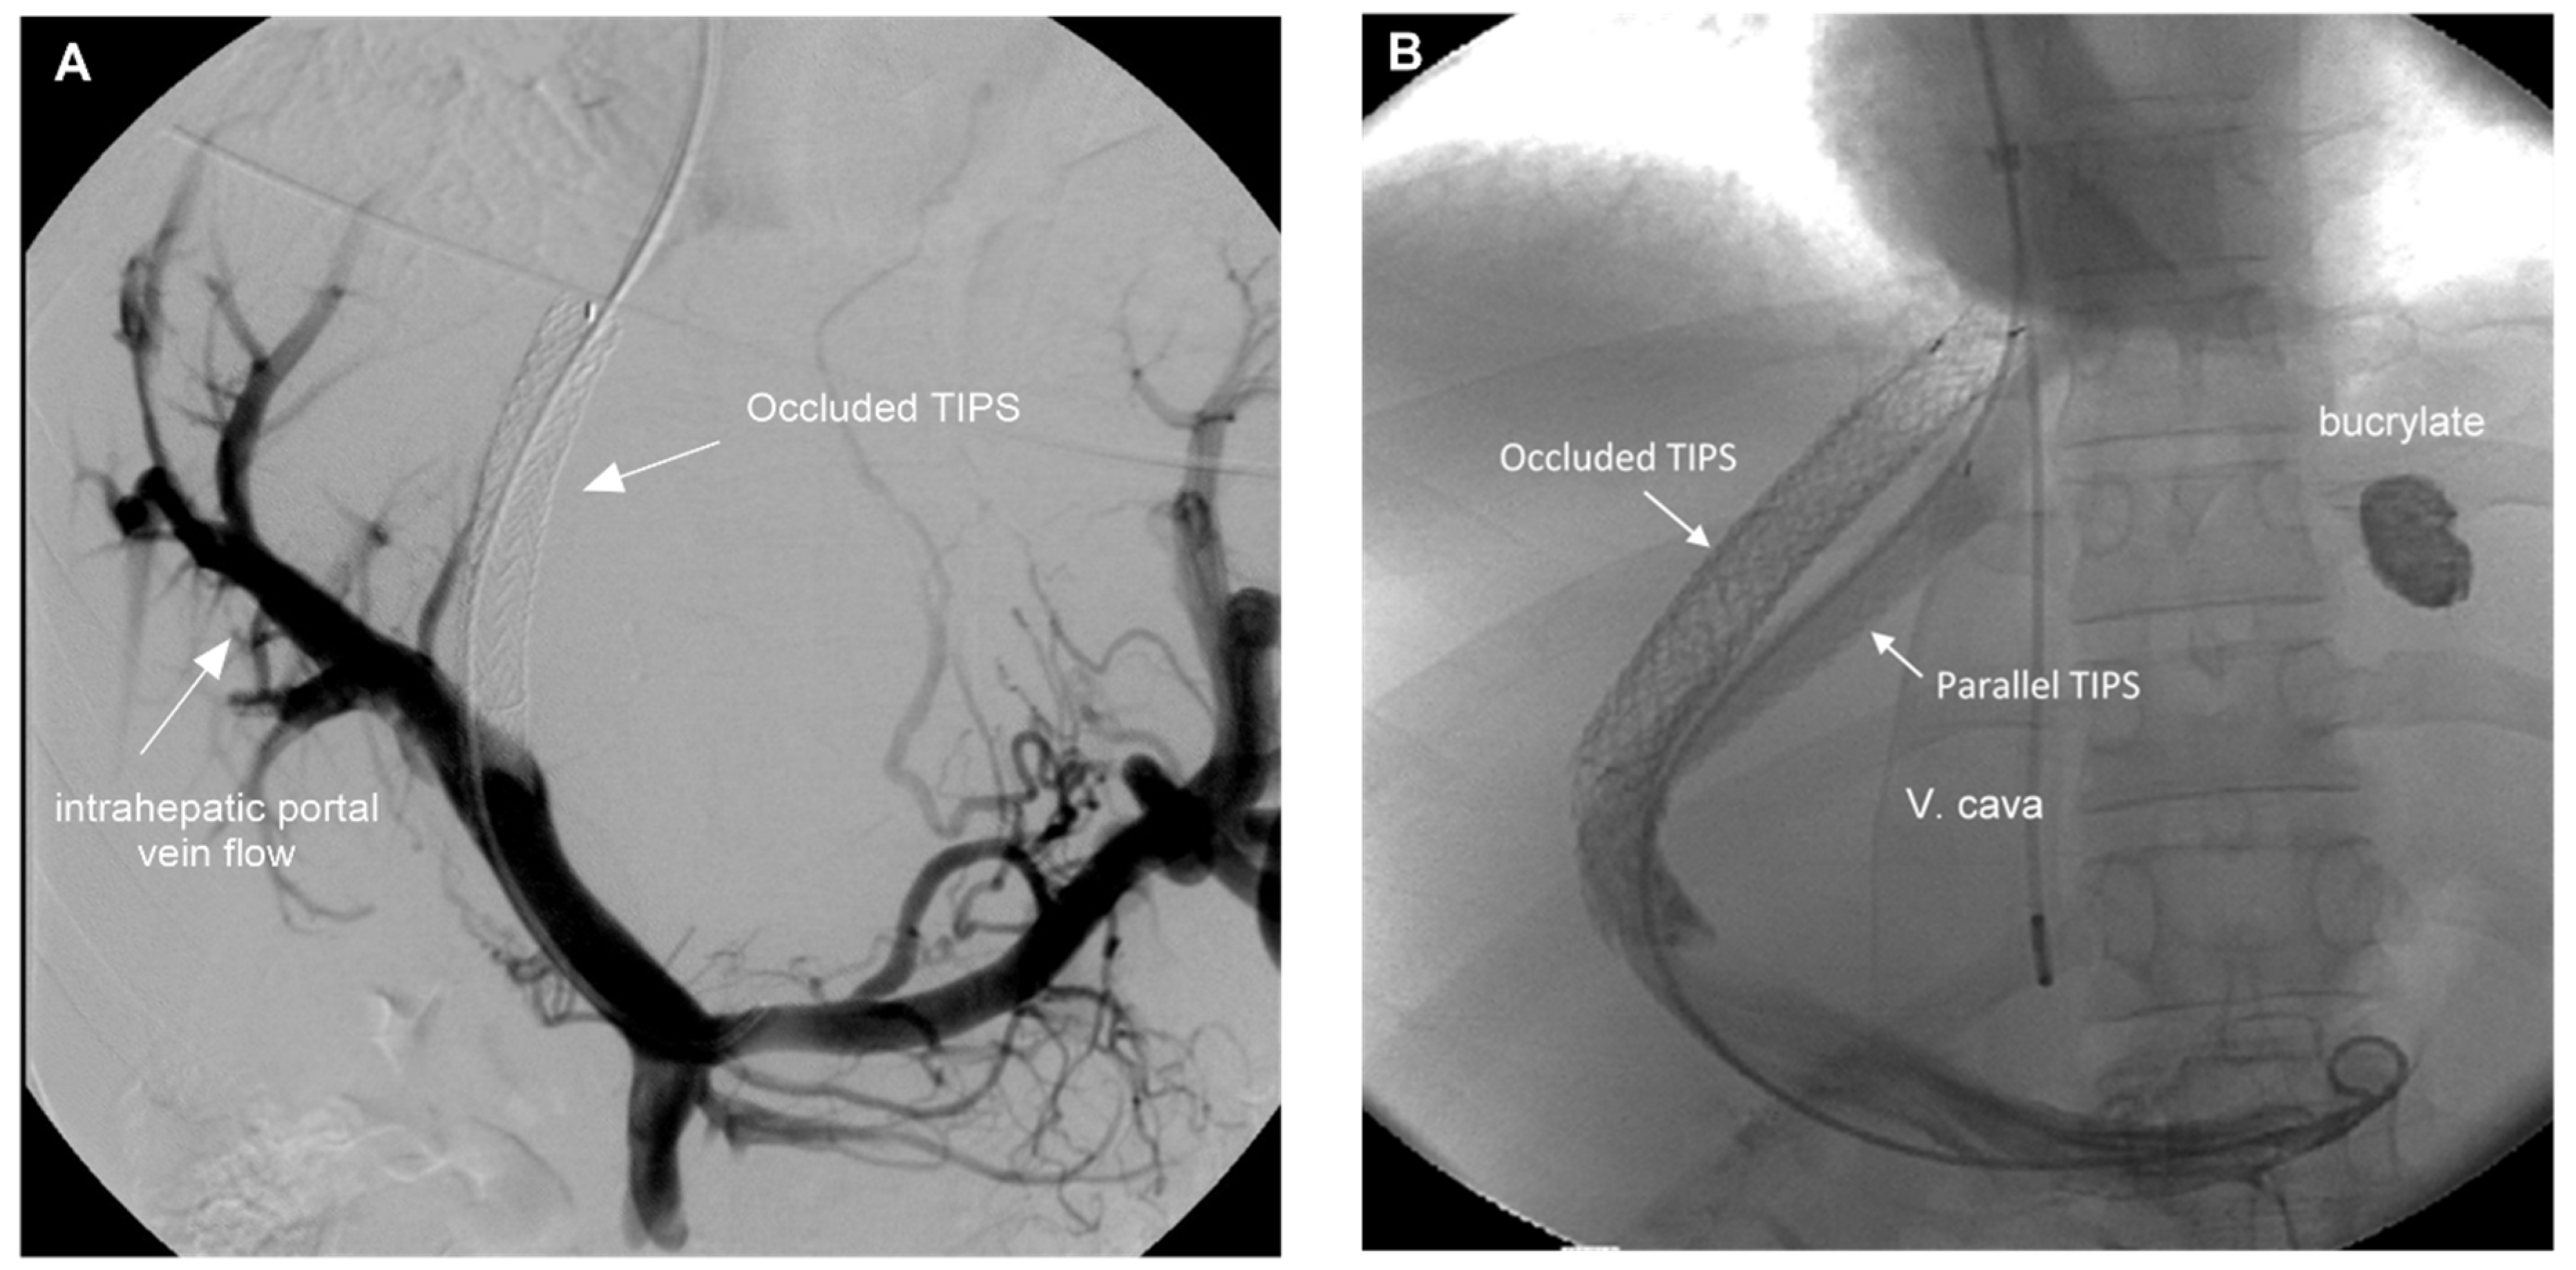

Shunt patency was controlled using CDUS immediately before TE examinations were performed. Primary shunt patency was observed in four patients. Twenty-one patients required a total of 49 revisions, with 2.0 ± 2.0 revisions per patient (1; 1–8). Patency was restored in 17 patients by stent-in-stent implantation or the placement of a parallel stent (n = 2). In four patients, radiological revision revealed pressure gradients below 12 mmHg, the reason why stent patency was not restored. Two characteristic examples are shown in Figure 1. In addition, sonographic examinations excluded ascites, hepatocellular carcinoma, and portal vein thrombosis.

Figure 1. (A). Portography of patient #17 five months after TIPS implantation. CDUS showed occluded TIPS in the absence of clinical signs of portal hypertension. The angiogram demonstrates good intrahepatic portal perfusion and the pressure gradient was 10 mmHg. The shunt was not restored and the catheter removed. (B). Portography of a 16-year-old female patient (#4) with fulminant BCS in 1998 requiring early TIPS implantation. After seven revisions between 1998 and 2013 a serious variceal bleeding from gastric varices occurred. The catheterization of the occluded stent-shunt was not possible and a transcaval puncture was performed to implant a parallel stent. The shunt has been fully patent since 2013 and the patient gave birth to a healthy child in 2019.